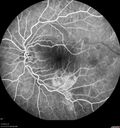

Bilateral Acute Central Serous Chorioretinopathy - Evidence of old disease OS333 views64 year old man noticed in the right eye that is a black spot 4 days ago. Also vertical lines in his kitchen were a little wavy. He is not on any steroid medications. He has vertigo.

VA OD: Dcc20/25-2 NccJ1+-3

VA OS: Dcc20/32-1 PHNI NccJ5-1

IOP: TP: OD:12 OS:15